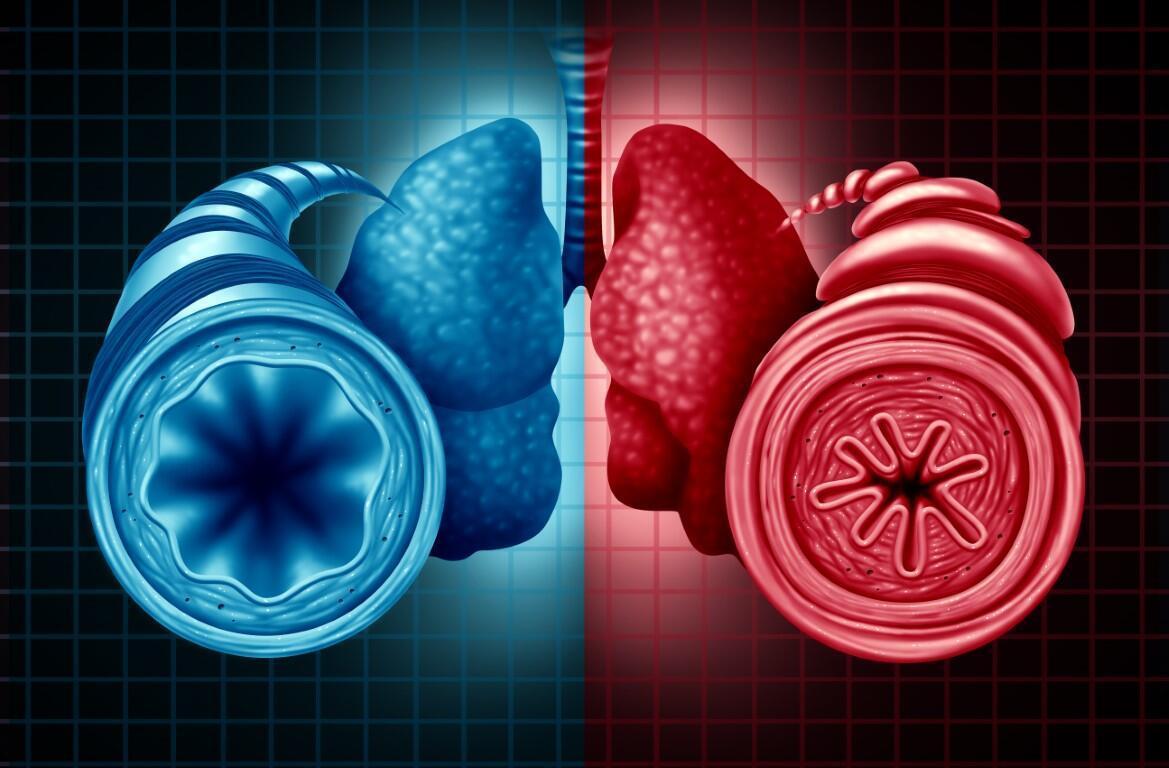

Astım bronşit akciğerlerde meydana gelen kronik bir hastalıktır ve yaşam kalitesini ciddi oranda düşürür. Akciğerlerimizin içindeki havayollarımızı oluşturan bronş adı veren kanallarda, alerjenlerin neden olduğu hasara bağlı olarak alerjik astım gelişir. Peki, astım bronşit hastaları ne gibi sorunlar yaşar? Astım bronşit belirtileri nelerdir?

Astım bronşların daralması sonucunda çoğu kez nöbetler halinde gelen nefes darlığı, göğüste sıkışma hissi ile birlikte hırıltılı-hışıltılı soluma ve arka arkaya gelen öksürüğün eşlik ettiği havayolu hastalığı olarak karşımıza gelir. Hava yollarındaki bu daralmanın nedeni mikrobik olmayan bir tür iltihap nedeniyle hava yolu duvarının şişmesidir. Hastalık tekrarlayan nefes darlığı, nefes alıp verirken ortaya çıkan hırıltı/hışıltı/ıslık sesi, göğüste baskı hissi ve öksürük gibi belirtilerle kendini gösterir.

Genellikle üst solunum yolu enfeksiyonlarına bağlı ataklar gösteren hastalık tekrarlayan nefes darlığı, nefes alıp verirken ortaya çıkan hırıltı/hışıltı/ıslık sesi, göğüste baskı hissi ve öksürük gibi belirtilerle kendini gösterir. Bronş gevşetici ilaçlarla şikayetler düzelse de küf/rutubet, kimyasal kokular ve hava kirliliği ile hastalık alevlenmesi görülebilir.